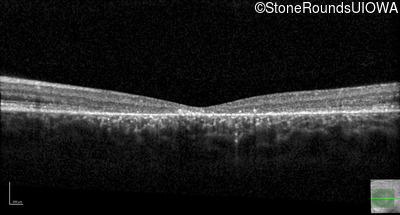

This 16 year old female first had difficulty seeing the blackboard at age 9. Her eye doctor at the time felt at the time that she was "faking it". More recently her eye doctor told her she would be blind by age 20 and suggested she get a seeing eye dog.

| AR Stargardt Disease | ABCA4 | Asp507Tyr GAT>TAT | IVS40+5 G>A | AR |